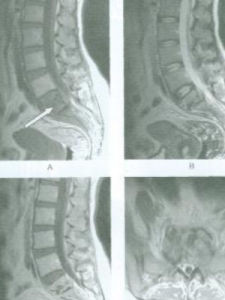

①碎片型:椎體破壞後留下小碎片,其椎旁有低密度的軟組織陰影,其中常有散在的小碎片;②溶骨型:椎體前緣或中心有溶骨性破壞區;③骨膜下型:椎體前緣有參差不齊的骨性破壞,椎旁軟組織中常可見環形或半環形鈣化影像;④局限性骨破壞型:破壞區周圍時有硬化帶(Jainr等1993)。脊椎結核CT檢查以碎片型最為常見,而脊椎腫瘤也常有與之相似之處,故應結合臨床資料綜合分析,如椎旁擴大陰影中,有鈣化灶或小骨碎片時,有助於脊椎結核的診斷。儘管如此分型,CT有時還是無法鑑別脊椎結核如脊椎腫瘤。MRI檢查具有軟組織高解析度的特點,用於顱腦和脊髓檢查優於CT,在脊椎矢面、軸面和冠面等均可掃描成像。脊椎結核MRI表現病變的椎體、間盤和附屬檔案與正常的脊椎對應處的正常信號相比,高於者為高信號,低於者為低信號。

1.椎體病變T1加權像顯示病變處為低信號,或其中雜有短T1信號。椎體病變T2加權像顯示信號增強。圖像顯示有病變椎體除信號改變外,可見椎體破壞的輪廓、椎體塌陷後順列改變和擴大的椎旁影像等。

2.椎旁膿腫脊椎結核椎旁膿腫在T1加權像顯示低信號,而T2加權像呈現較高信號。冠面能描繪出椎旁膿腫或雙側腰大肌膿腫的輪廓與範圍。

3.椎間盤改變脊椎結核X線攝片間盤變窄是早期徵象之一。MRI的T1加權像呈現低信號變窄的間盤。正常的髓核內在T2加權像有橫行的細縫隙,當有炎症時這細縫隙消失,能早期發現間盤炎症改變。

MRI在早期脊椎結核的診斷較其他任何影像學檢查包括ECT在內更為敏感。臨床症狀出現3~6個月,疑內脊椎結核病人,X線攝片無異常,MRI可顯示受累椎體及椎旁軟組織(膿腫),T1加權像為低信號,T2加權像為高信號。早期脊椎結核MRI影像可分為三型。①椎體炎症;②椎體炎症合併膿腫;③椎體炎症、膿腫合併椎間盤炎。值得提出受累椎體處於炎症期,而無軟組織和椎間盤信號改變者,不能與椎體腫瘤相鑑別,必要時應行活檢證實。